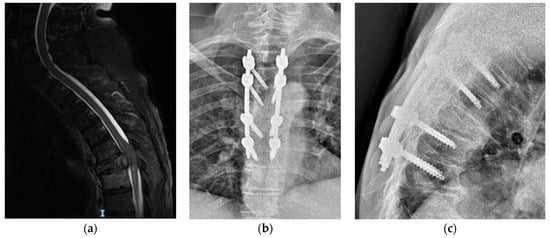

2.3. Surgical Technique